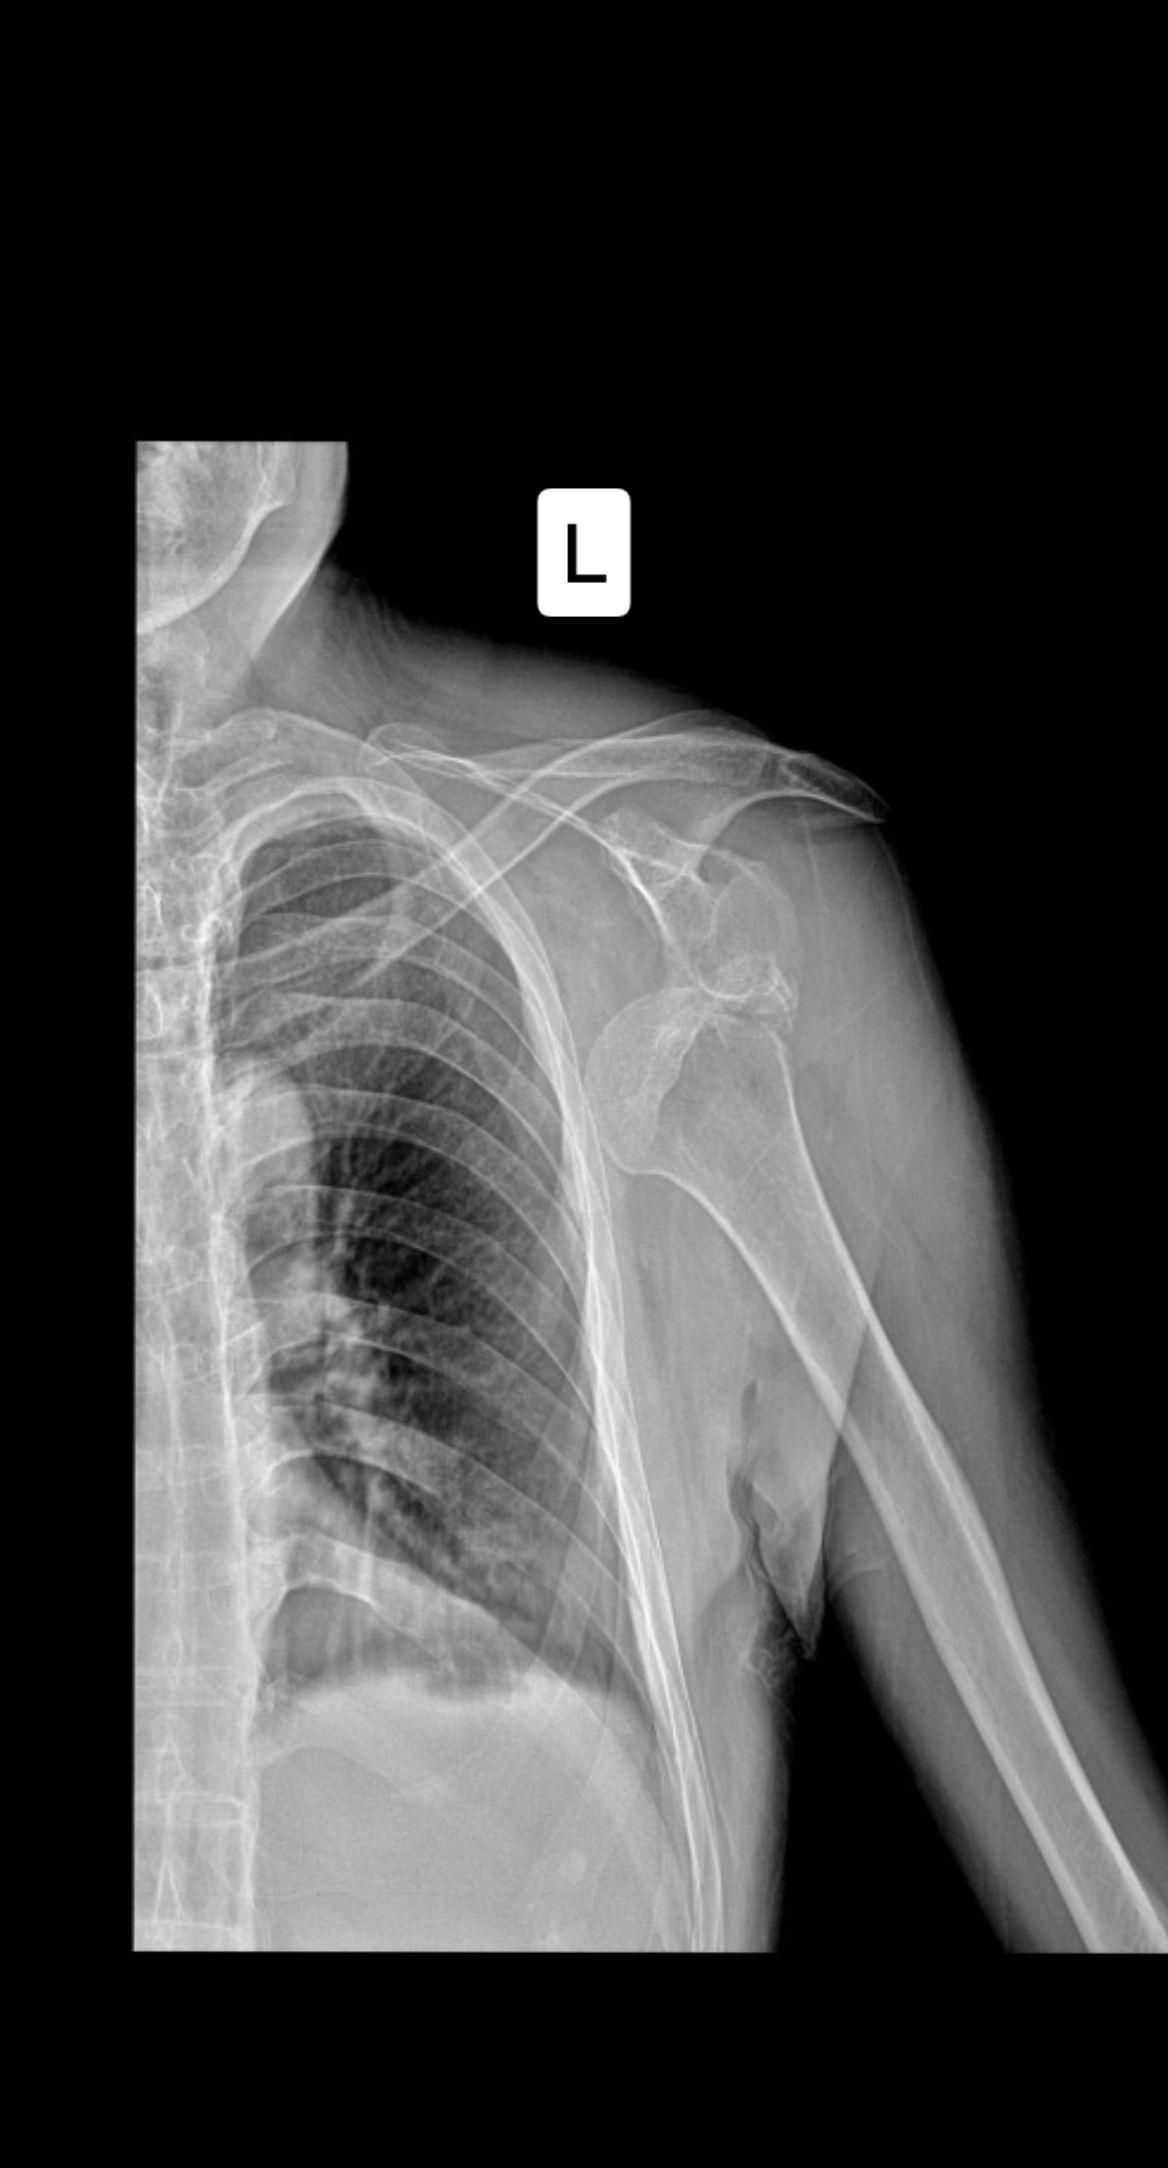

肩关节脱位?